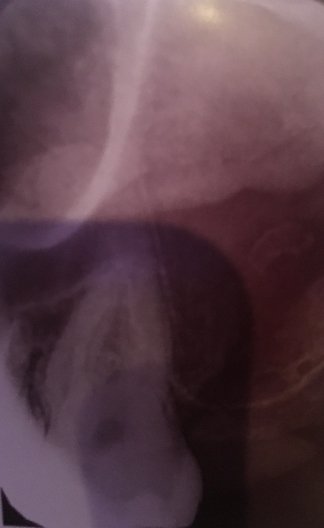

Здравствуйте! Есть ли у меня киста? Если да, то как срочно нужно делать операцию и как она называется?

Какой зуб вы имеете ввиду? Уточните. 18 и 48 зуб необходимо удалить. Далее расскажу после уточнения.